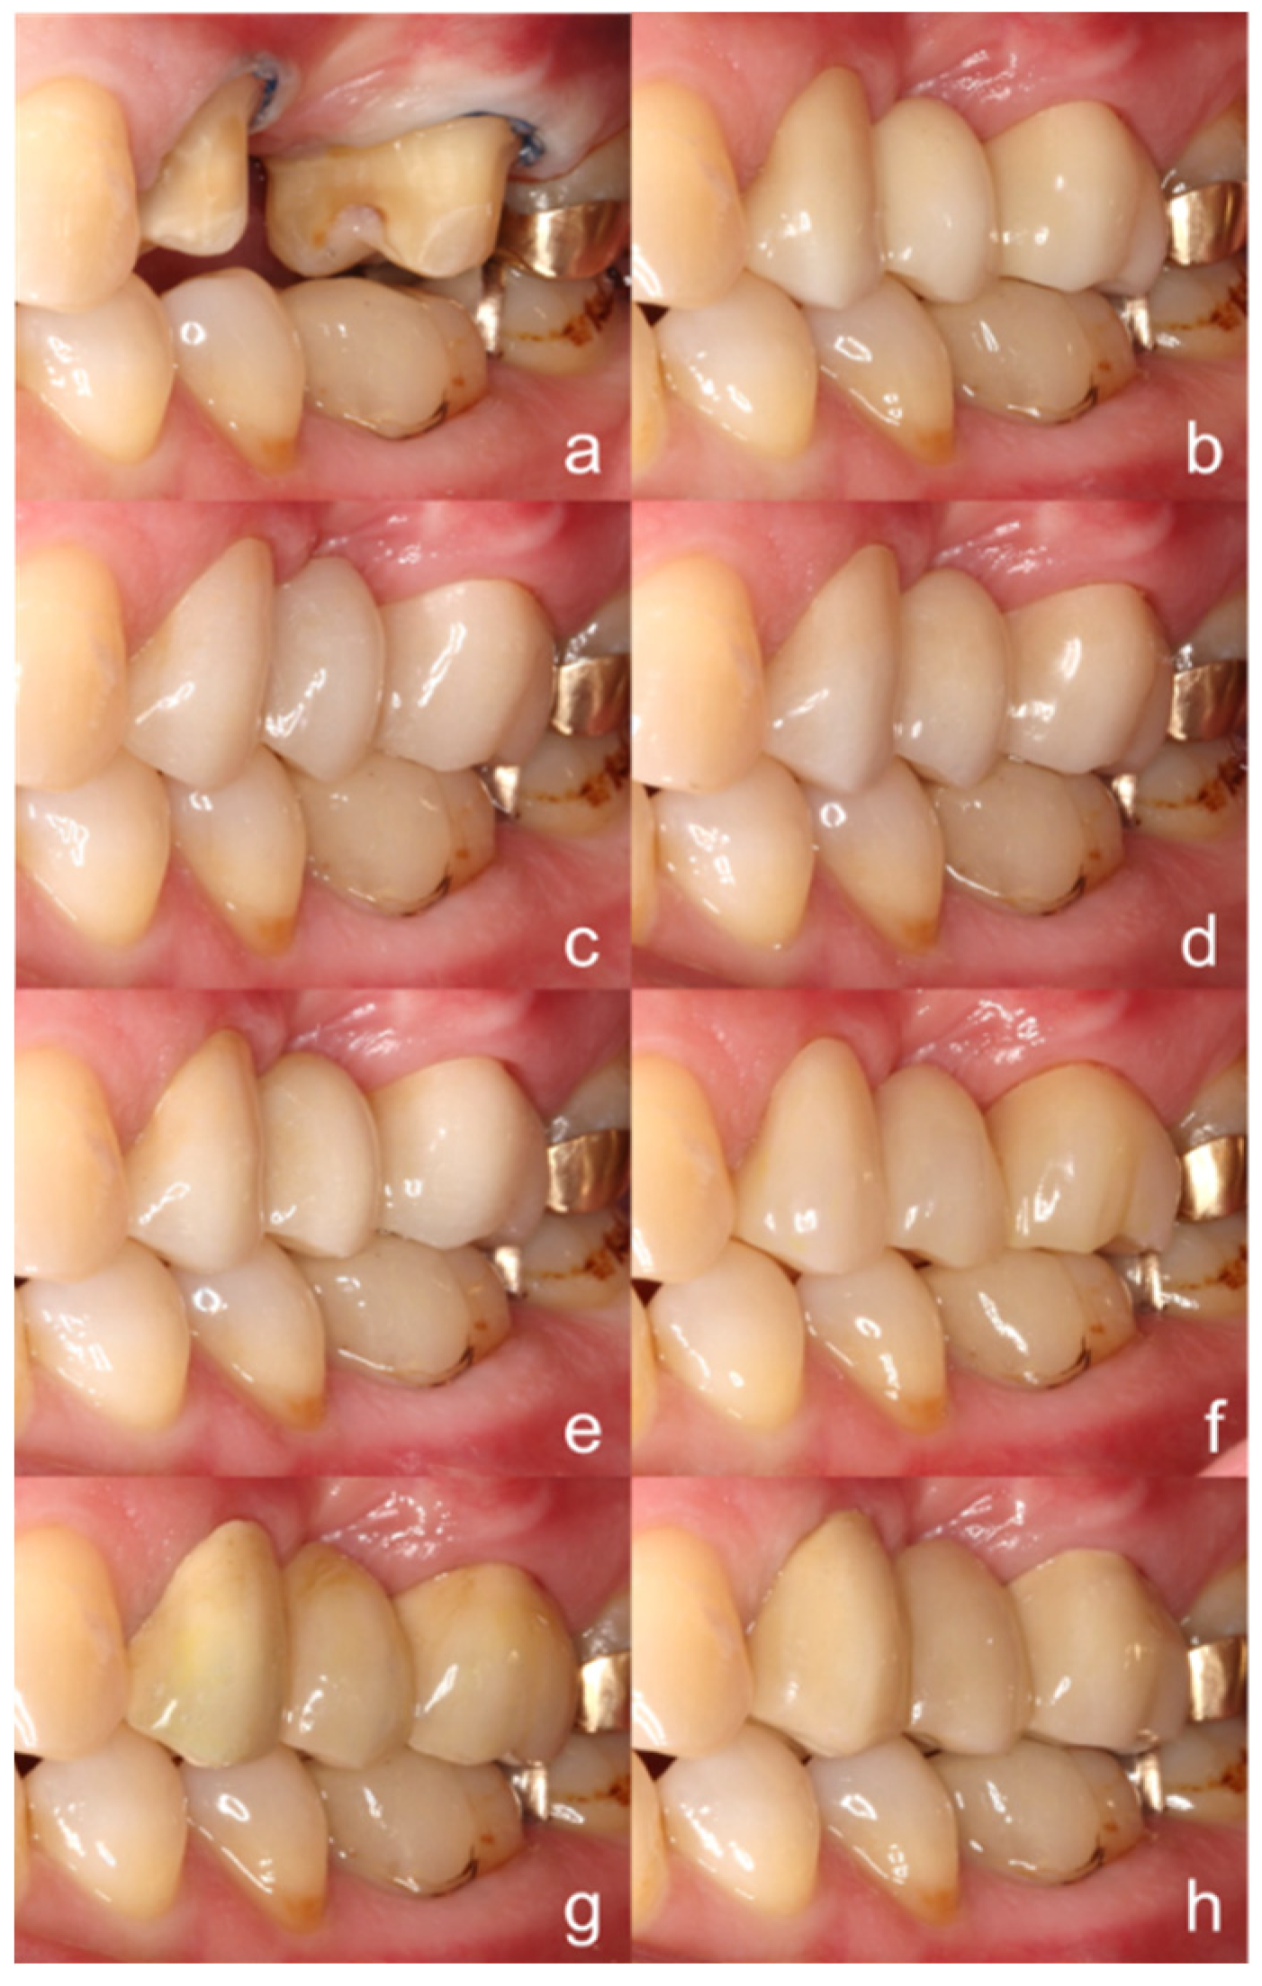

2. Materials and Methods

3. Results